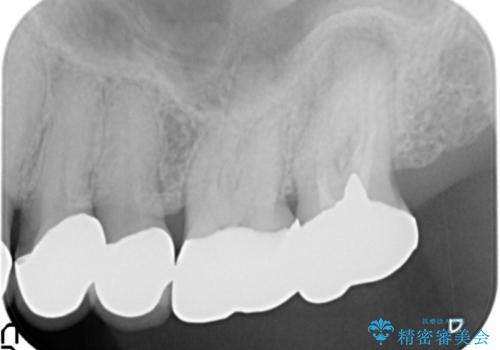

- 左上の一番奥の歯の根の治療を行いつつ、手前の歯の被せ物のやり直しも一緒に行いました。

根の治療は当法人の根管治療の認定医である林先生にお願いしました。